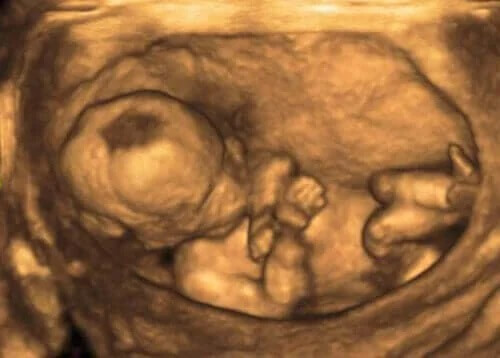

Läkare upptäcker vanligtvis dessa förändringar genom ett ultraljud för att mäta volymen fostervätska. De ser det genom ett fostervattensindex (FVI).

För att få fram rätt information delar läkaren in livmodern i fyra obegränsade kvadranter, som mäts i centimeter. Ett normalt FVI är mellan 8 och 21 cm.